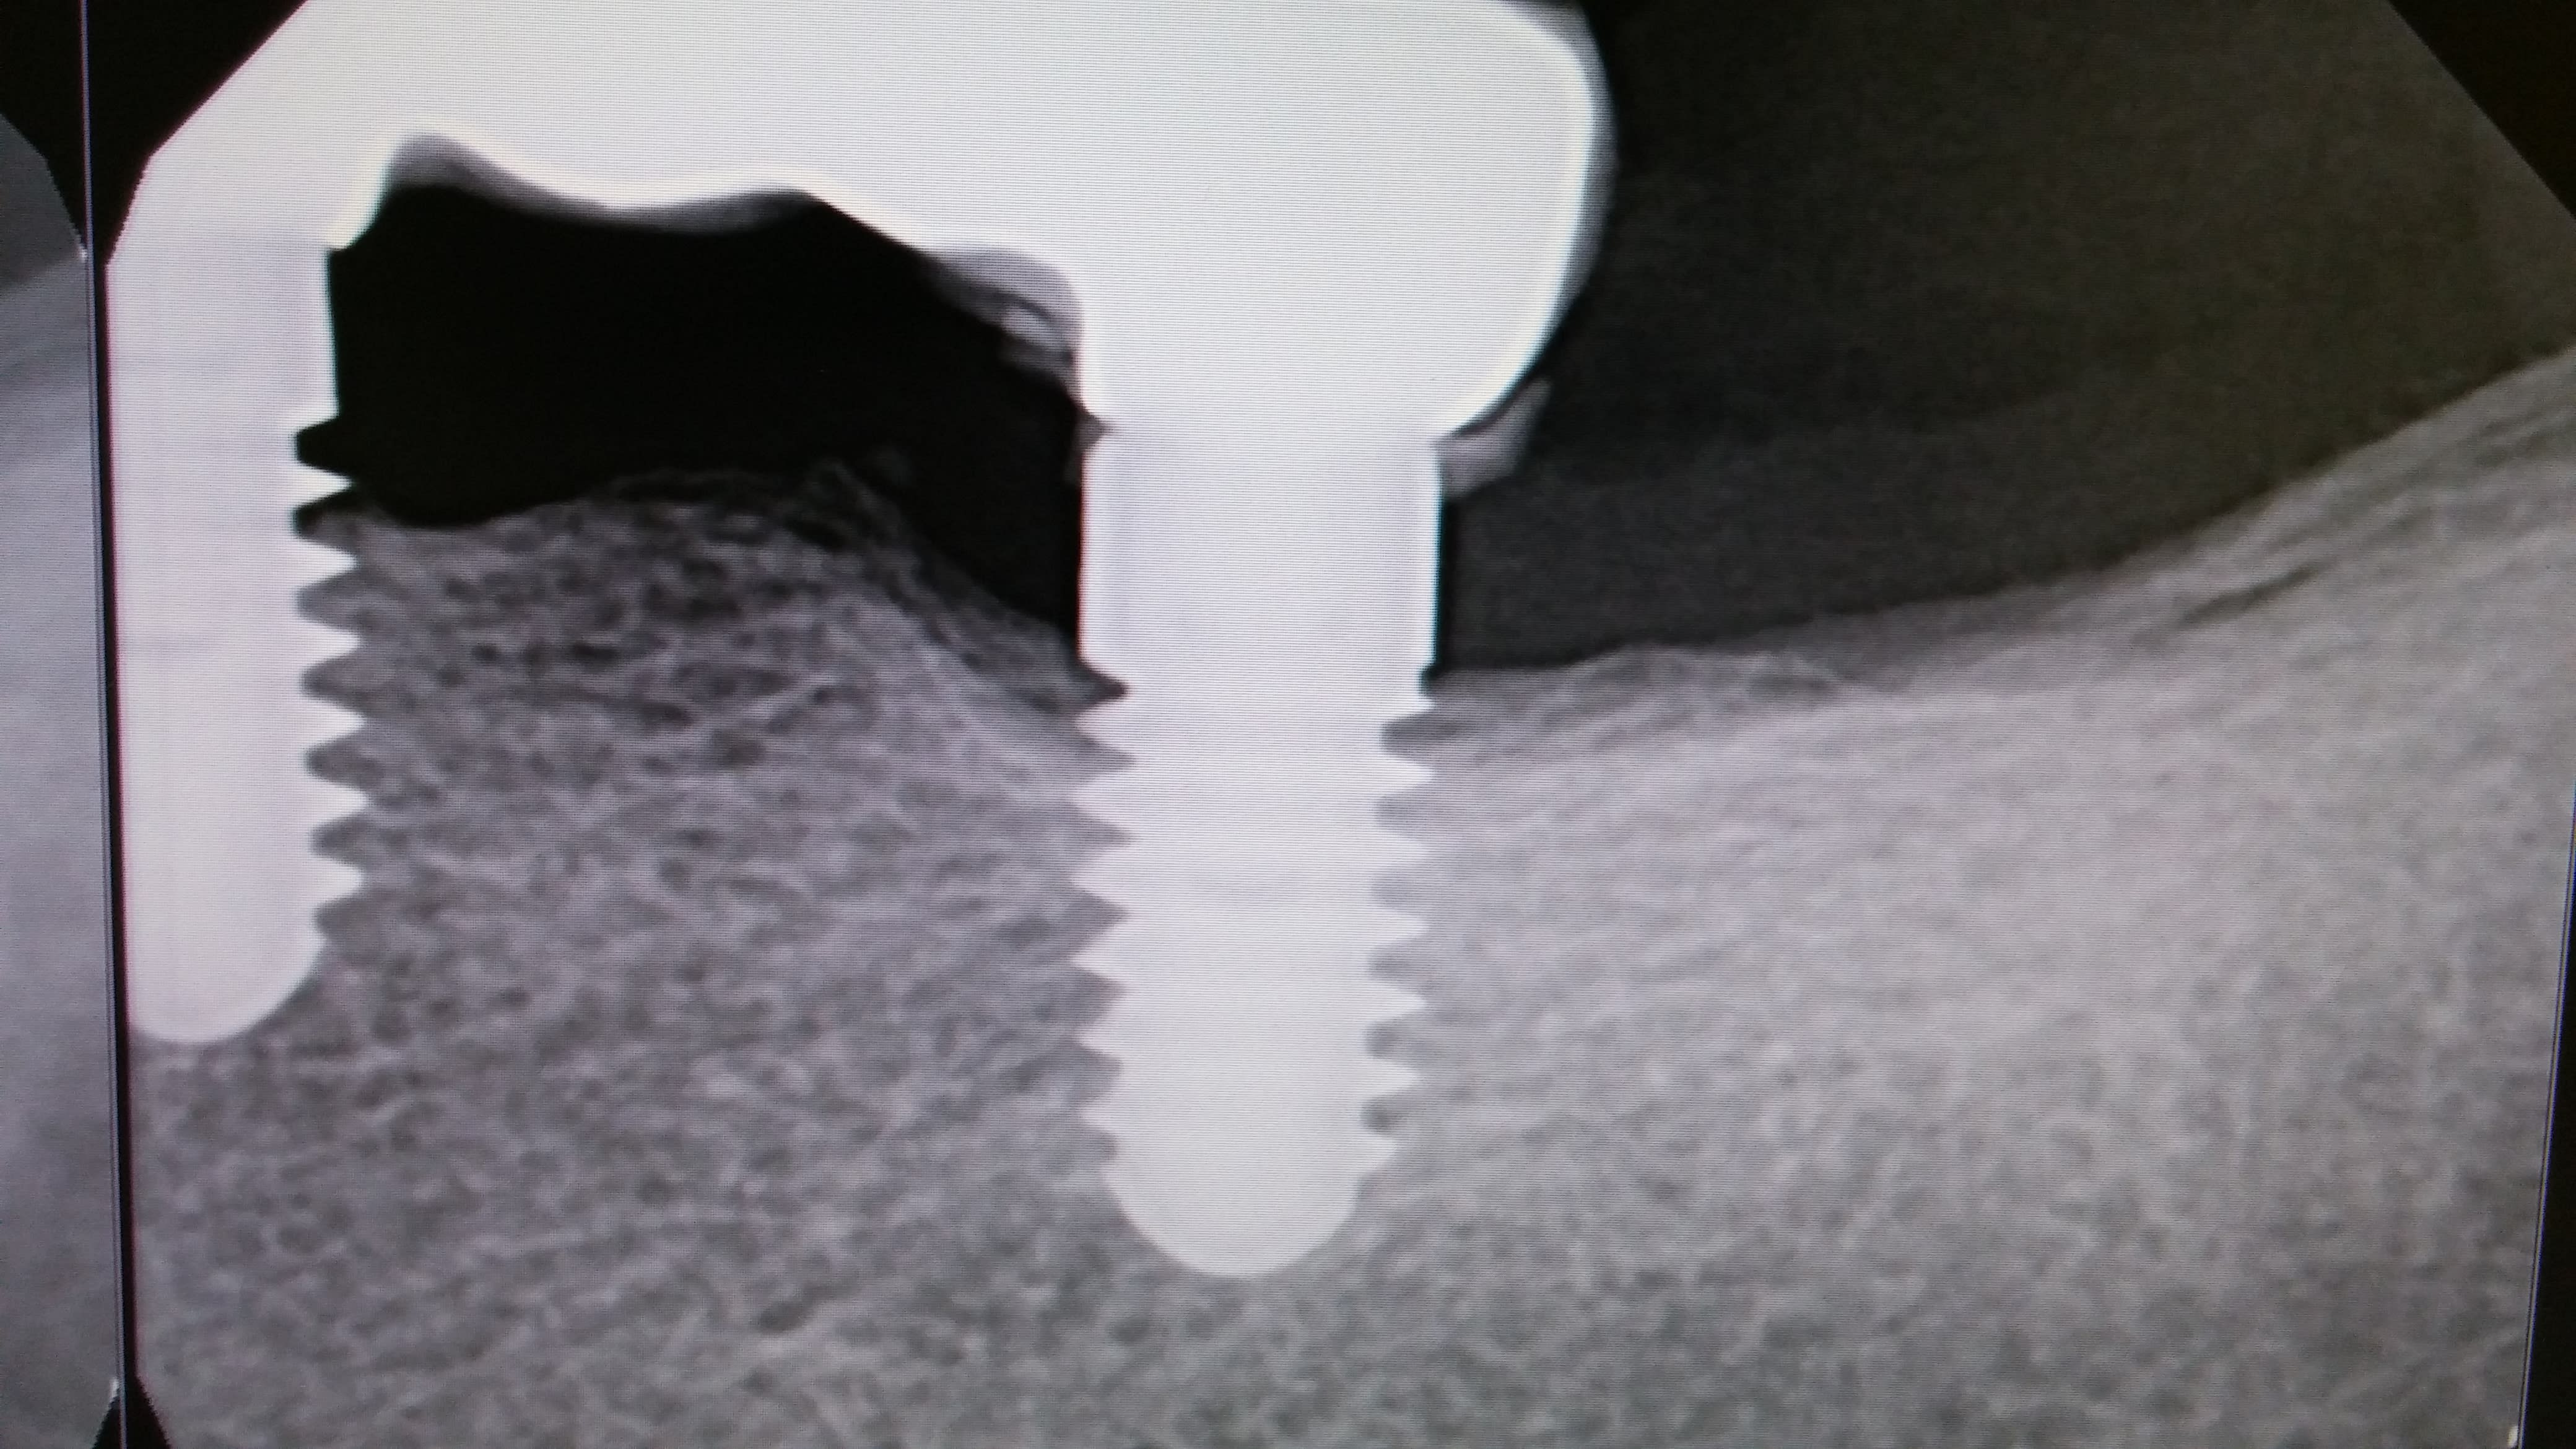

Vu hier en consult

Posés en Italie il y a 12+ ans

Vis cassée en mésial, "scellé" un urg il y a 2 mois dans une autre clinique, ça bouge encore...

Je connais pas ces implants...